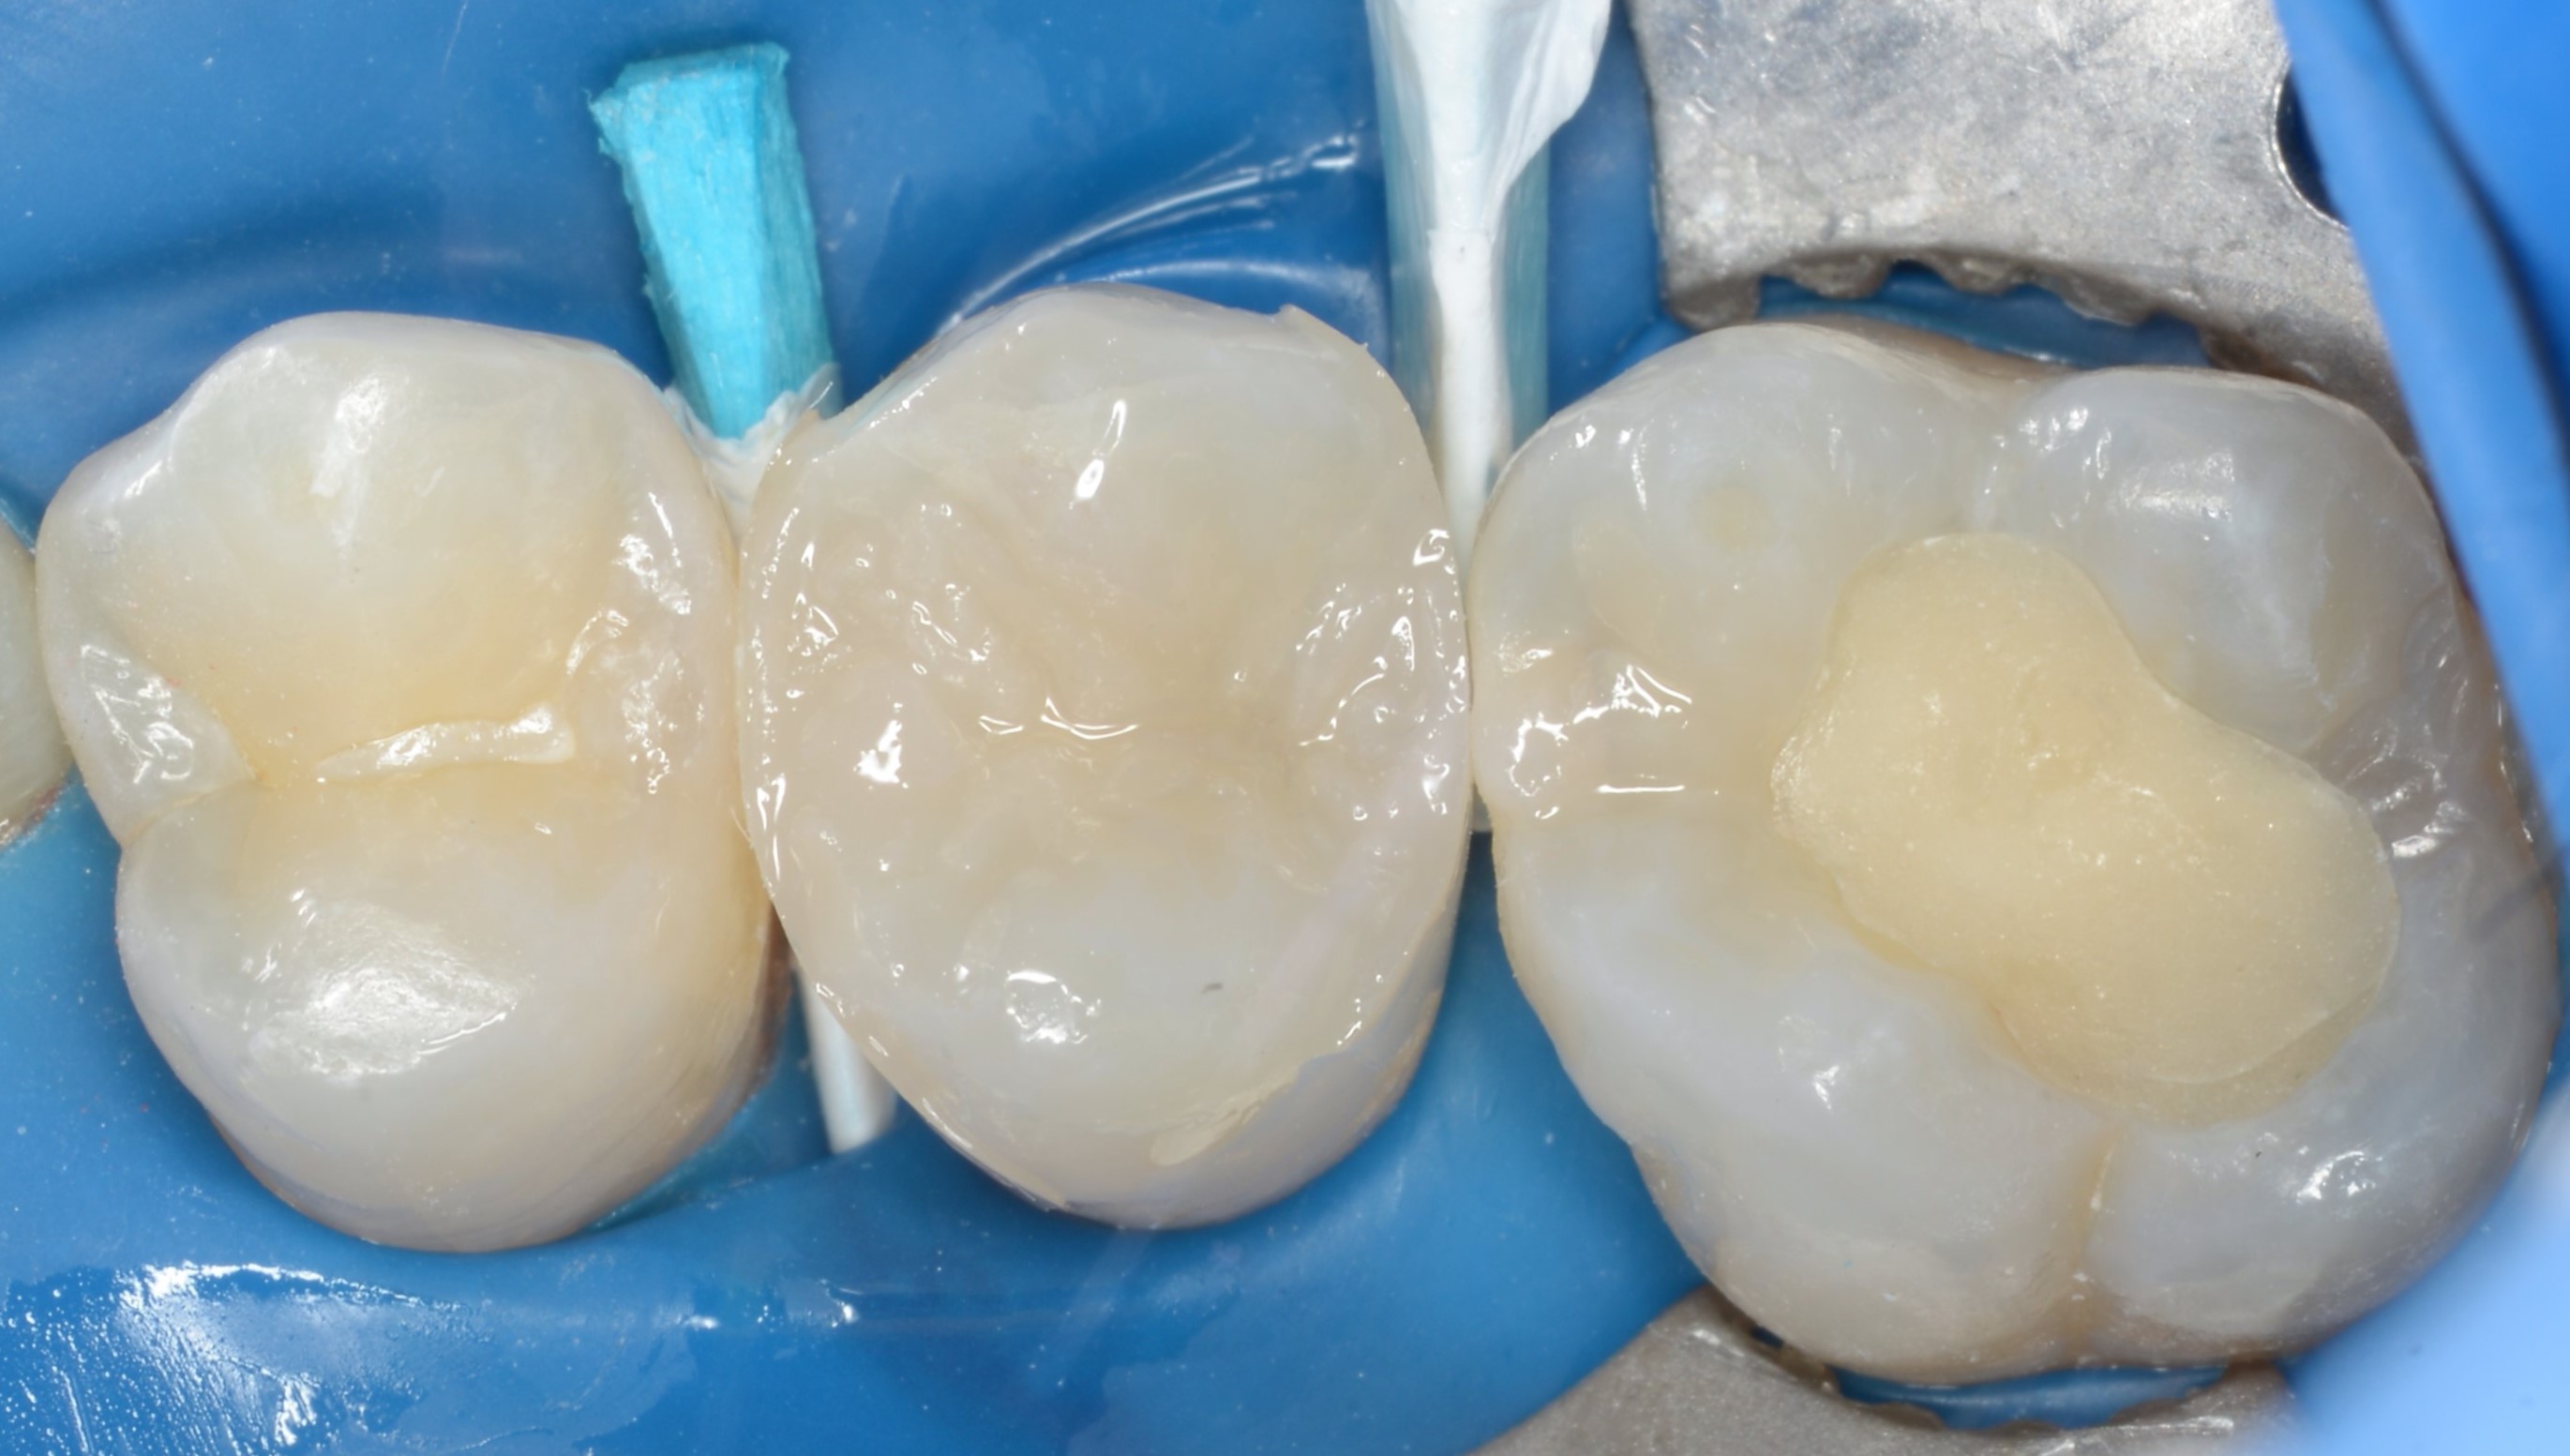

W celu zabezpieczenia biomateriału przed nadmiarem wilgoci zastosowano jednobuteleczkowy, samotrawiący, uniwersalny system wiążący Clearfil Universal Bond Quick (Kuraray Noritake) (ryc. 4). Prosta i szybka aplikacja oraz wysoka zawartość monomeru 10-MDP pozwala na trwałe, chemiczne wiązanie z wapniem w MTA oraz zębinie (2-4). Miejsce obnażenia pokryto płynnym materiałem kompozytowym w kolorze niebieskim (Color Flow, Cerkamed) (ryc. 5).

Ryc. 4. Aplikacja systemu wiążącego Clearfil Universal Bond Quick (Kuraray Noritake) na całą zębinę i materiału Color Flow (Cerkamed) na miejsce przykrycia miazgi.

Ryc. 5. Zabezpieczenie hydrofilnego systemu wiążącego Clearfil Universal Bond Quick (Kuraray Noritake) kompozytem płynnym Clearfil Majesty ES Flow Super Low A2 (Kuraray Noritake) na całej powierzchni zębiny.

W celu zwiększenia konwersji monomeru w dnie ubytku, przeprowadzono dwa cykle polimeryzacji (Valiant LED, VISTA USA), rozdzielone chłodzeniem zęba powietrzem ze strzykawki wodno-powietrznej (3, 4). W celu zabezpieczenia warstwy hybrydowej na resztę zębiny zaaplikowano materiał kompozytowy typu flow o zwiększonej ilości napełniacza Clearfil Majesty ES Flow Super Low w kolorze A2 (Kuraray Noritake). Do wysokości niepodpartego szkliwa na powierzchni mezjalnej zrąb zębinowy odbudowano materiałem kompozytowym typu bulk fill – OliBulk Fill MD (Olident) (ryc. 6). Ze względu na nietolerancję długich zabiegów przez pacjenta, spowodowaną trudnościami w oddychaniu w pozycji leżącej, ubytek zaopatrzono materiałem tymczasowym (Cavit, 3M) i odroczono ostateczną odbudowę.

Ryc. 6. Wypełnienie zrębu zębinowego do wysokości niepodpartej listwy szkliwnej kompozytem płynnym typu bulk-fill OliBulk Fill MD (Olident).